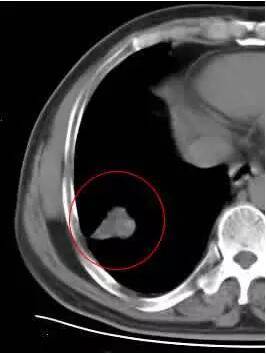

五、空泡征

结节内小灶透光区,直径小于5MM,多见于腺癌和细支气管肺泡癌,CT检查:发生率为24-48%。 空泡征的病理基础:未被肿瘤组织占据的肺组织,未闭合的细支气管,乳头状癌结构间的含气腔隙,未闭或融解、破坏、扩大的肺泡腔 。